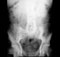

Urinary bladder: Observe peritoneal coverings of the urinary bladder. Note the different reflection in male and female. Remove the peritoneum and identify the urachus (median umbilical ligament). Examine the musculature of the bladder wall and identify the ureteric orifices, the interureteric crest, the urethral orifice, and the trigone. In the male look for a uvula. Blood supply, innervation and lymphatic drainage of the bladder will be exposed in a later dissection.

Urinary bladder 4. Examine the male genital tract, remove endopelvic fascia surrounding seminal vesicles. (Play movie; View images: N 352, 359, 361A, 361B, 362, 363, 365, 384A, 384B, TG 5-07, 6-07, 6-08, 6-09, 6-10, 6-14, 6-15, 6-31)